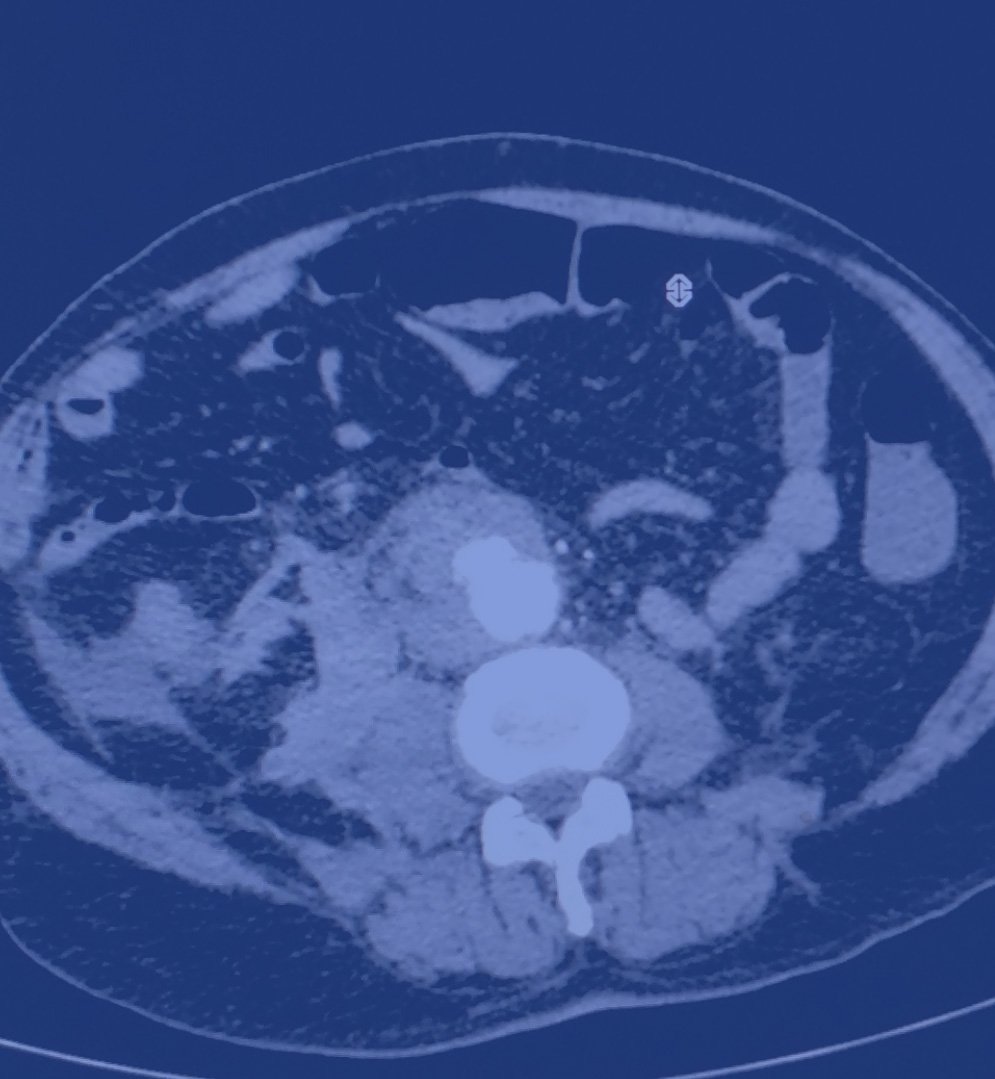

Πώς γίνεται η διάγνωση;

- Με υπερηχογράφημα κοιλίας (triplex) ή αξονική αγγειογραφία, ανάλογα με την ανατομική θέση.

- Η αξονική τομογραφία είναι απαραίτητη για προεγχειρητικό σχεδιασμό.

- Βάσει της ακριβούς ανατομίας του ανευρύσματος από αξονική αγγειογραφία υψηλής ανάλυσης.

- Απαιτεί προσεκτικό σχεδιασμό με εξειδικευμένα λογισμικά και προσαρμοσμένες ενδοπροθέσεις.